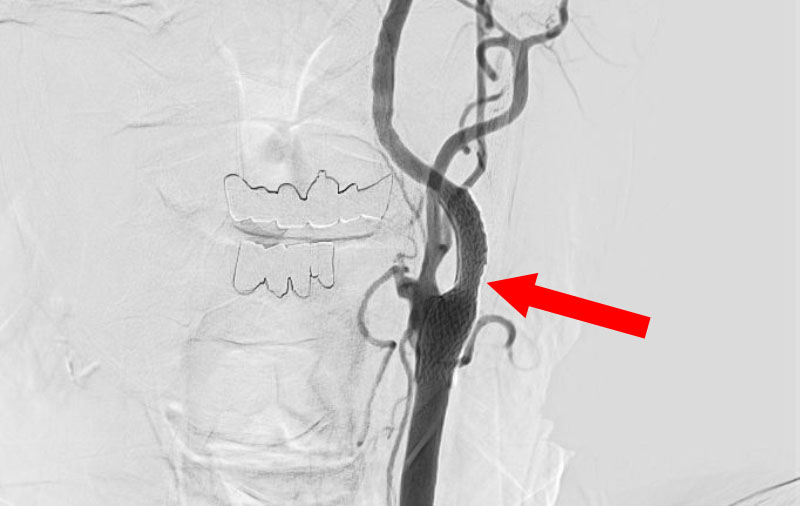

'24年10月

左内頚動脈後交通動脈

分岐部動脈瘤

50代

大阪府の病院

No.1508 手術前

No.1508 手術中

No.1508 手術後